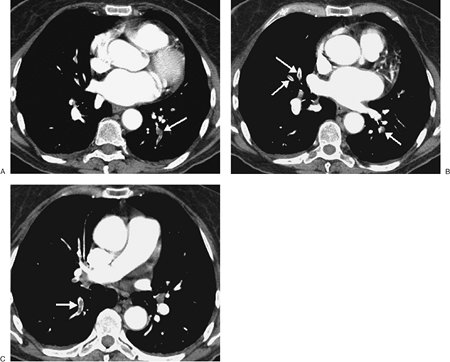

FIGURE 17-27. Primary pulmonary arterial hypertension. A: PA chest radiograph of a 54-year-old woman shows enlargement of the pulmonary arteries (arrows) and cardiac enlargement. B: CT confirms enlargement of the main (PA), right, and left pulmonary arteries. Note that the main pulmonary artery is larger in diameter than the adjacent ascending aorta. Systolic and diastolic pulmonary artery pressures were 97 mm Hg and 53 mm Hg, respectively, with a mean pressure of 70 mm Hg. C: CT at a more inferior level shows enlargement of the right atrium (RA) and right ventricle (RV).